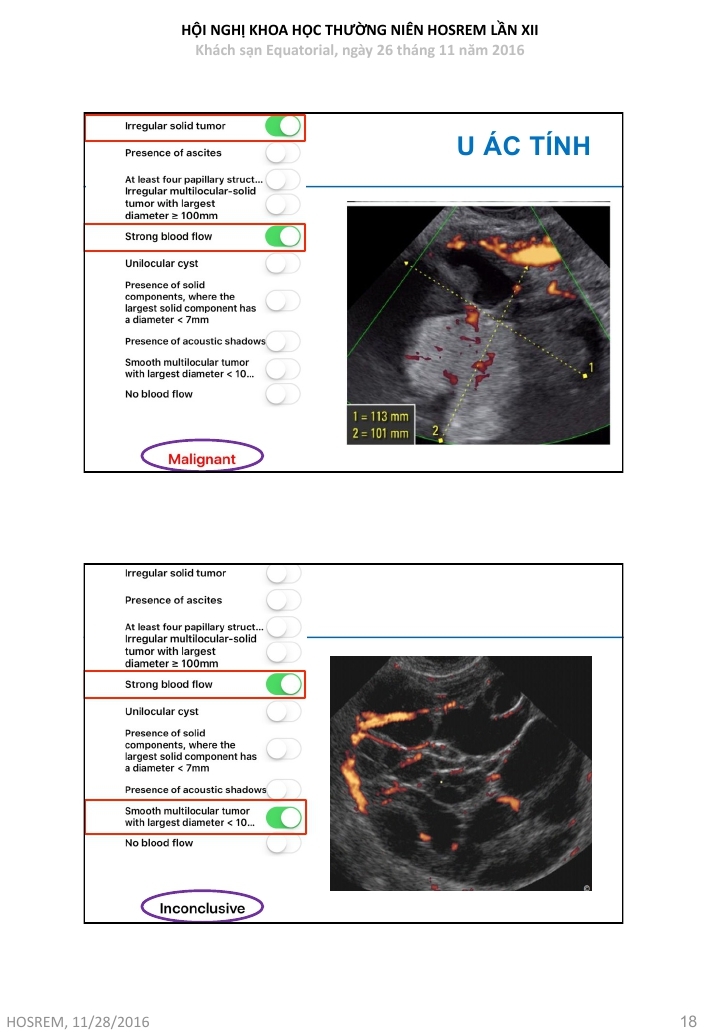

Ung thư buồng trứng  chẩn đoán và đánh giá nguy cơ ác tính theo IOTA

Từ khóa: Ung thư buồng trứng chẩn đoán và đánh giá nguy cơ ác tính theo IOTA